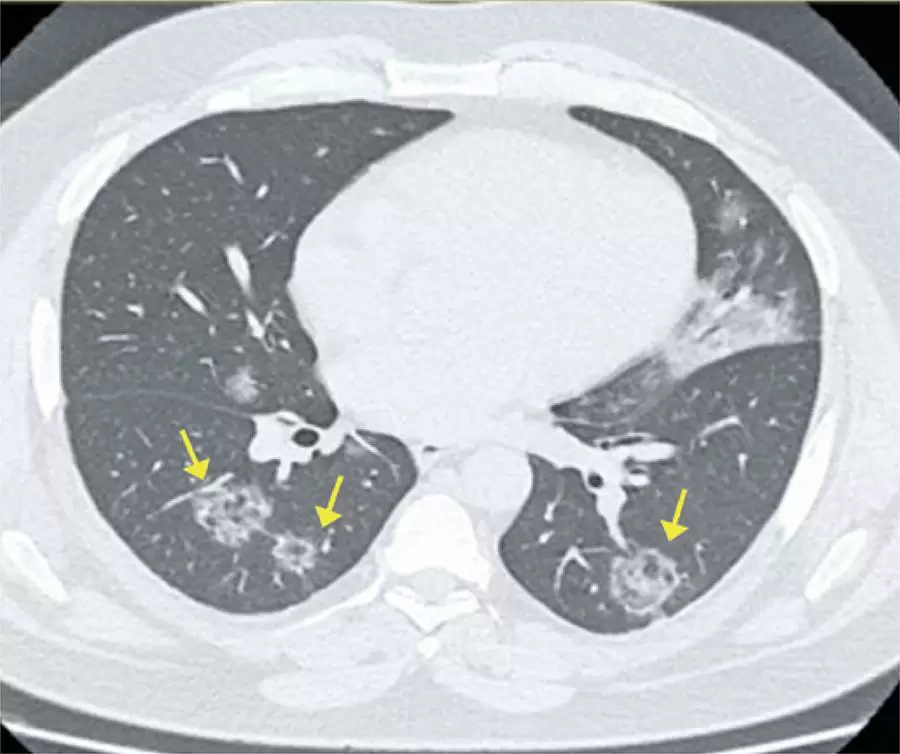

Achados da COVID-19 identificados na tomografia computadorizada de tórax: ensaio pictórico

A doença causada pelo novo coronavírus, ou COVID-19, foi descrita recentemente e tornou-se uma questão de saúde mundial. Seu diagnóstico de certeza é dado pela reação em cadeia da polimerase. A tomografia computadorizada de alta resolução, entretanto, mostra-se útil no contexto atual de pandemia, especialmente nos casos mais graves, na avaliação da extensão da doença, em possíveis diagnósticos diferenciais e na pesquisa de complicações. Em pacientes com quadro clínico suspeito e achados de imagem típicos, nos quais ainda não há resultado laboratorial ou a reação em cadeia da polimerase não se encontra disponível, ainda se discute o papel desse exame. Importante ressaltar que parte dos pacientes apresenta exames laboratoriais falsos-negativos, notadamente em casos iniciais, o que pode retardar medidas de isolamento, favorecendo a propagação da doença. Dessa forma, o conhecimento da COVID-19 e de suas manifestações nos exames de imagem é de extrema importância para os médicos envolvidos no atendimento, sejam clínicos ou radiologistas.